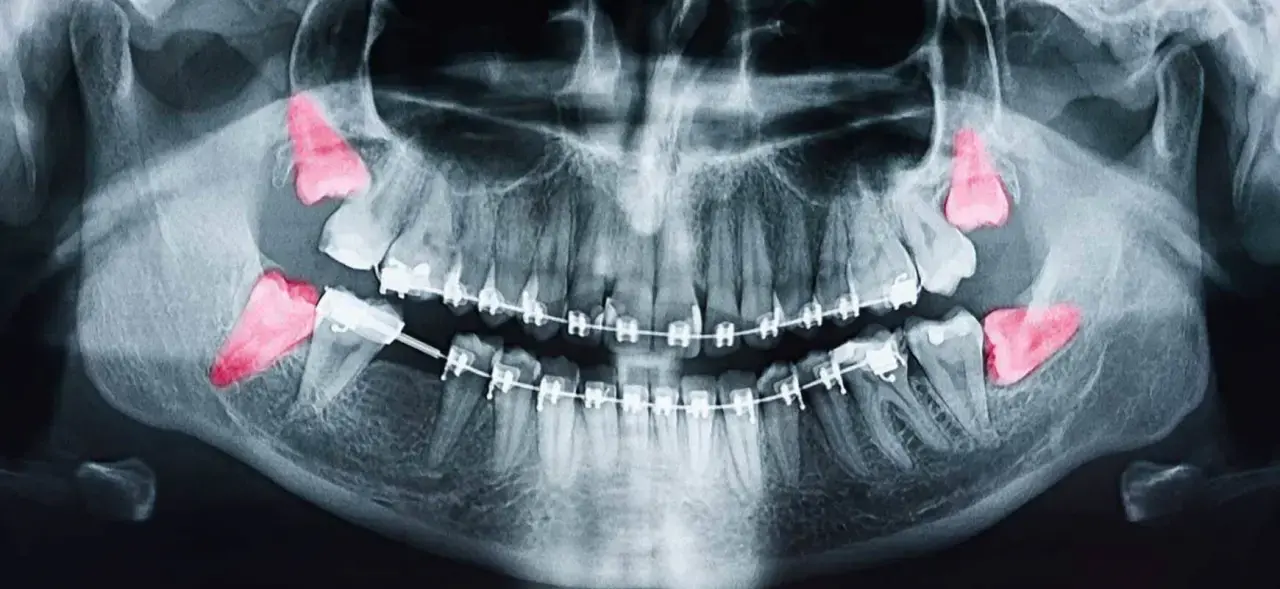

Muayene ve röntgen: İlk olarak panoramik röntgen çekilerek dişin konumu belirlenir.

Gömülü 20 yaş dişleri potansiyel olarak tehlikelidir. Her ne kadar bazı kişilerde uzun yıllar belirti vermeden kalabilse de, riskli durumların ortaya çıkma ihtimali oldukça yüksektir. Özellikle kısmen gömülü dişlerde enfeksiyon, şiddetli ağrı ve çürük sorunları çok sık görülür. Dolayısıyla, gömülü 20’lik dişlerin düzenli aralıklarla panoramik röntgen ile takip edilmesi gerekir. Hekimler çoğu zaman bu dişlerin çekilmesini önerir. Çünkü sorun ortaya çıktıktan sonra yapılacak tedavi hem daha zor hem de daha ağrılı olabilir.